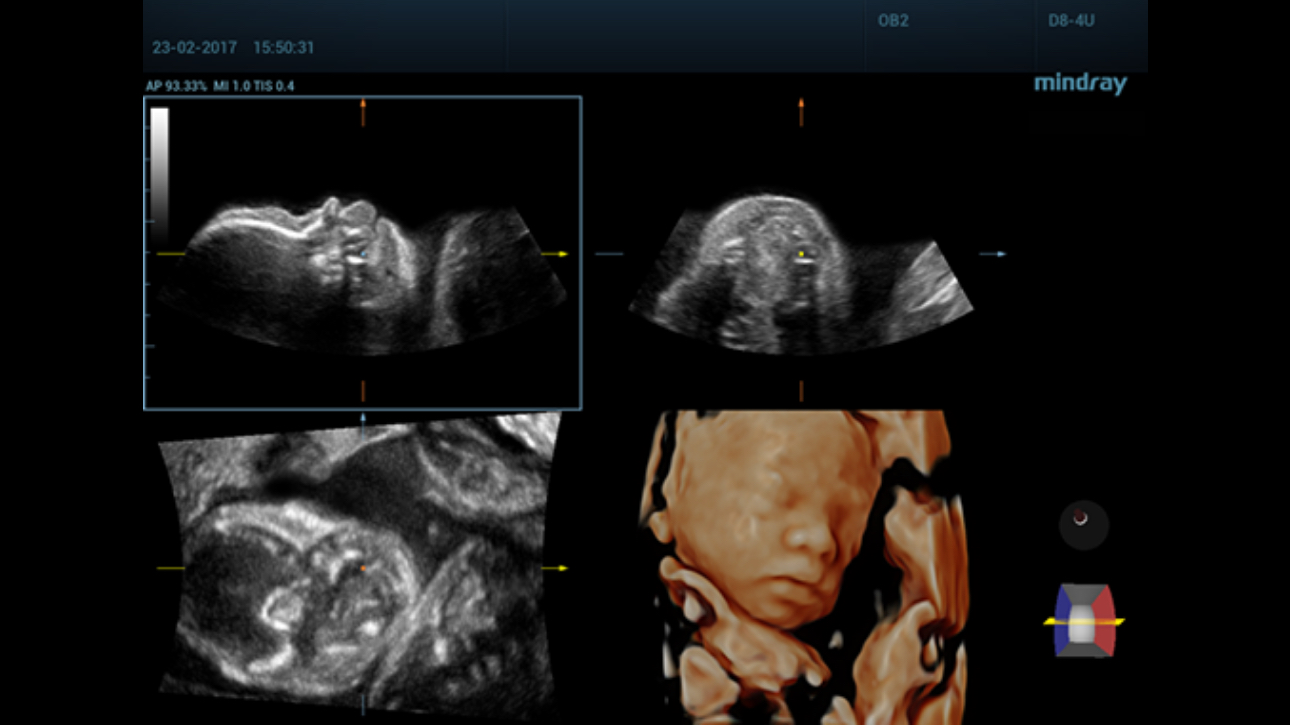

The channel data based ZST+?is an extraordinary innovation, representing an ultrasound evolution. Transforming ultrasound metrics from conventional beamforming to channel data based processing, ZST+?is more powerful and flexible to integrate the latest innovative OB/GYN imaging technologies, and to deliver a higher level of imaging performance in 2D, 3D/4D, and even the coronal plane image.

Comprehensive upgrading on iLive to significantly improve the detailed resolution as well as anatomical realism. Hyaline is a new rendering method that dynamically applies transparency to rendered structures for a more comprehensive view of anatomy, therefore better displaying internal anatomy from a solid surface.